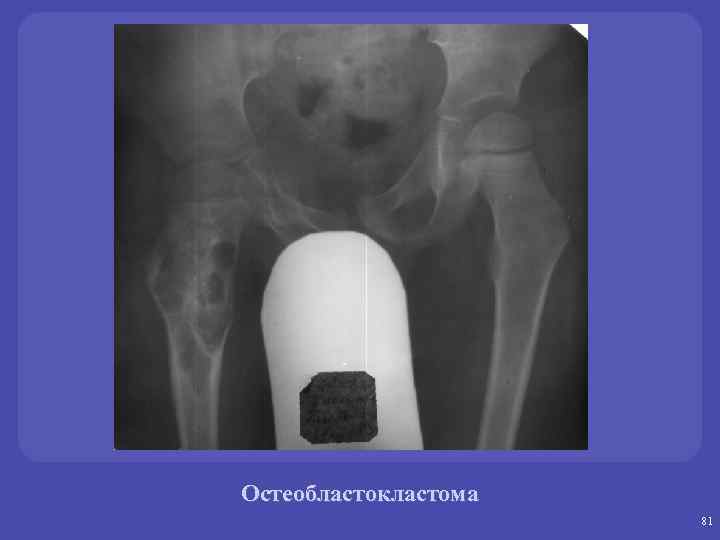

Остоебластокластомы. üГигантоклеточная опухоль. Микроскопически: одноядерные клетки (остеобласты), многоядерные гигантские клетки (остеокласты). üОпухоль собственно костной ткани, существующая как в доброкачественном, так и в злокачественном варианте. üЛокализация – дети - эпифиз, взрослые – метаэпифиз. Изолированно в диафизе не возникает. üФормы-пассивно –кистозные, активнокистозные, литические.

Остеобластокластома 79

Остеобластокластома 80

Остеобластокластома 81

Остеобластокластома 82